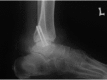

Abstract: Total talus dislocation is a rare injury and is commonly accompanied by associated fractures. Common worrisome sequelae are infection, avascular necrosis and post-traumatic arthritis. We report here on a patient who sustained an open total talus dislocation with an ipsilateral medial malleolus fracture. Following early debridement, reduction and a combination of internal and external fixations, early recovery was good with no evidence of avascular necrosis.